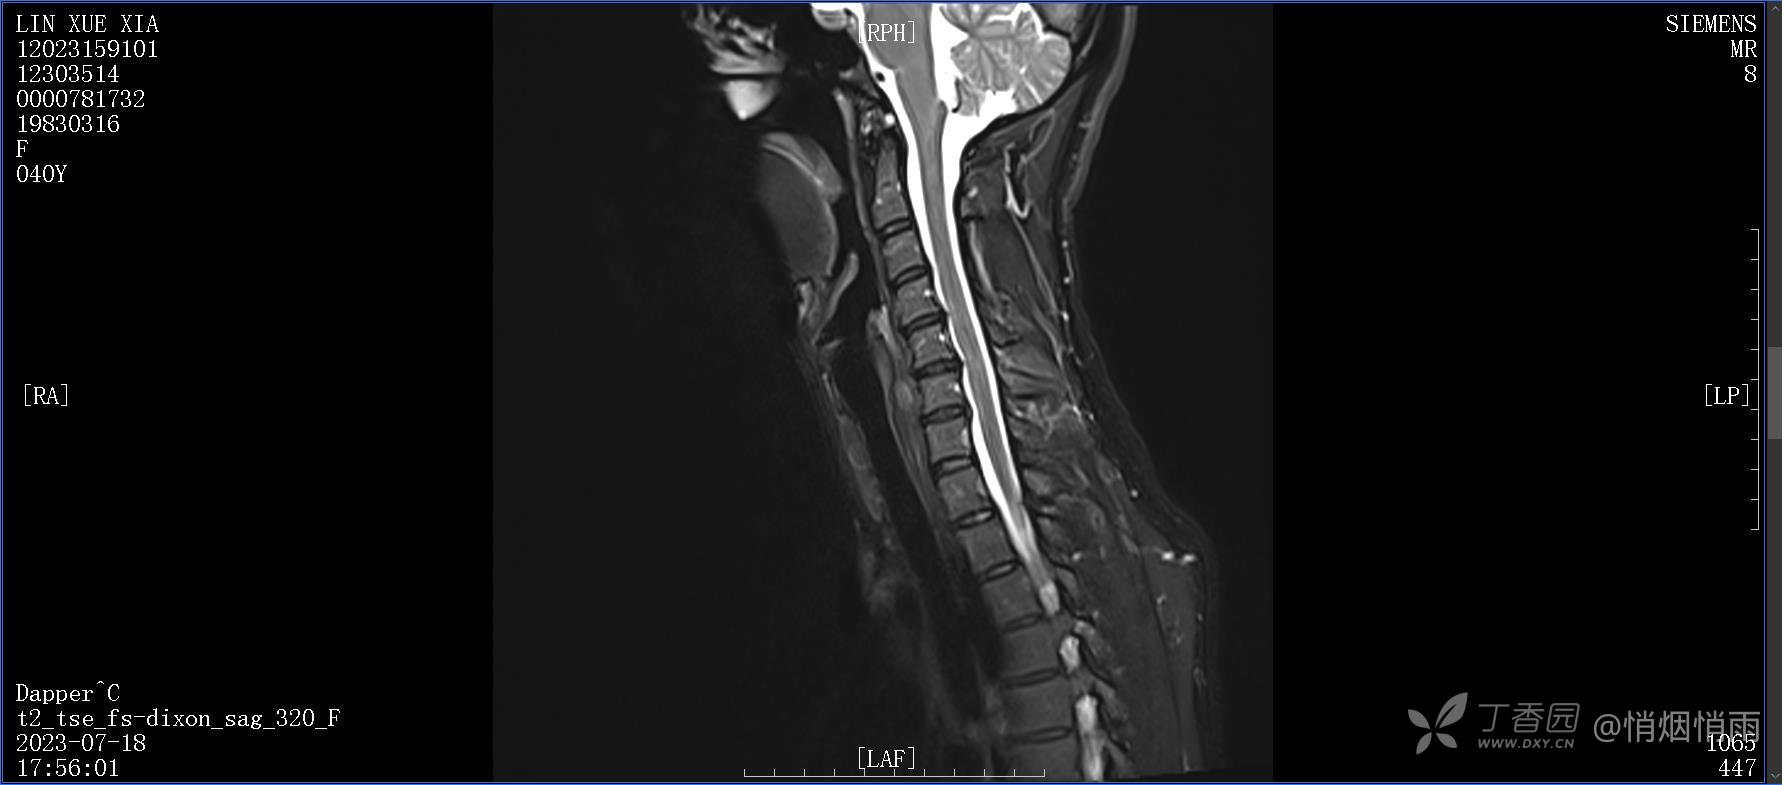

NeurothinkerZ 推荐患者女性,40岁,因右肩背部疼痛班活动受限4日余入院(2023-07-17)。

查体:右肩关节局部轻度肿胀,肩胛区压痛明显,痛处不固定,肩关节痛性活动受限,jobe test(+),lift -off test(+),中指、环指感觉较余指减退,余肢端感觉及血运情况可。

目前的诊断,暂时依据辅助检查诊为肩袖损伤,但是患者疼痛的性质和特点,却不是单纯的肩袖损伤所致。考虑过胸廓出口综合征,但是该疾病会出现肩胛区的疼痛吗?(由于考虑到费用的问题,没再进行下一步的检查)带状疱疹会有如此的症状吗?